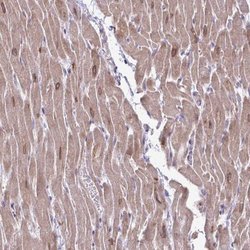

Immunohistochemistry

ABIN4278926 IHC

Other validation